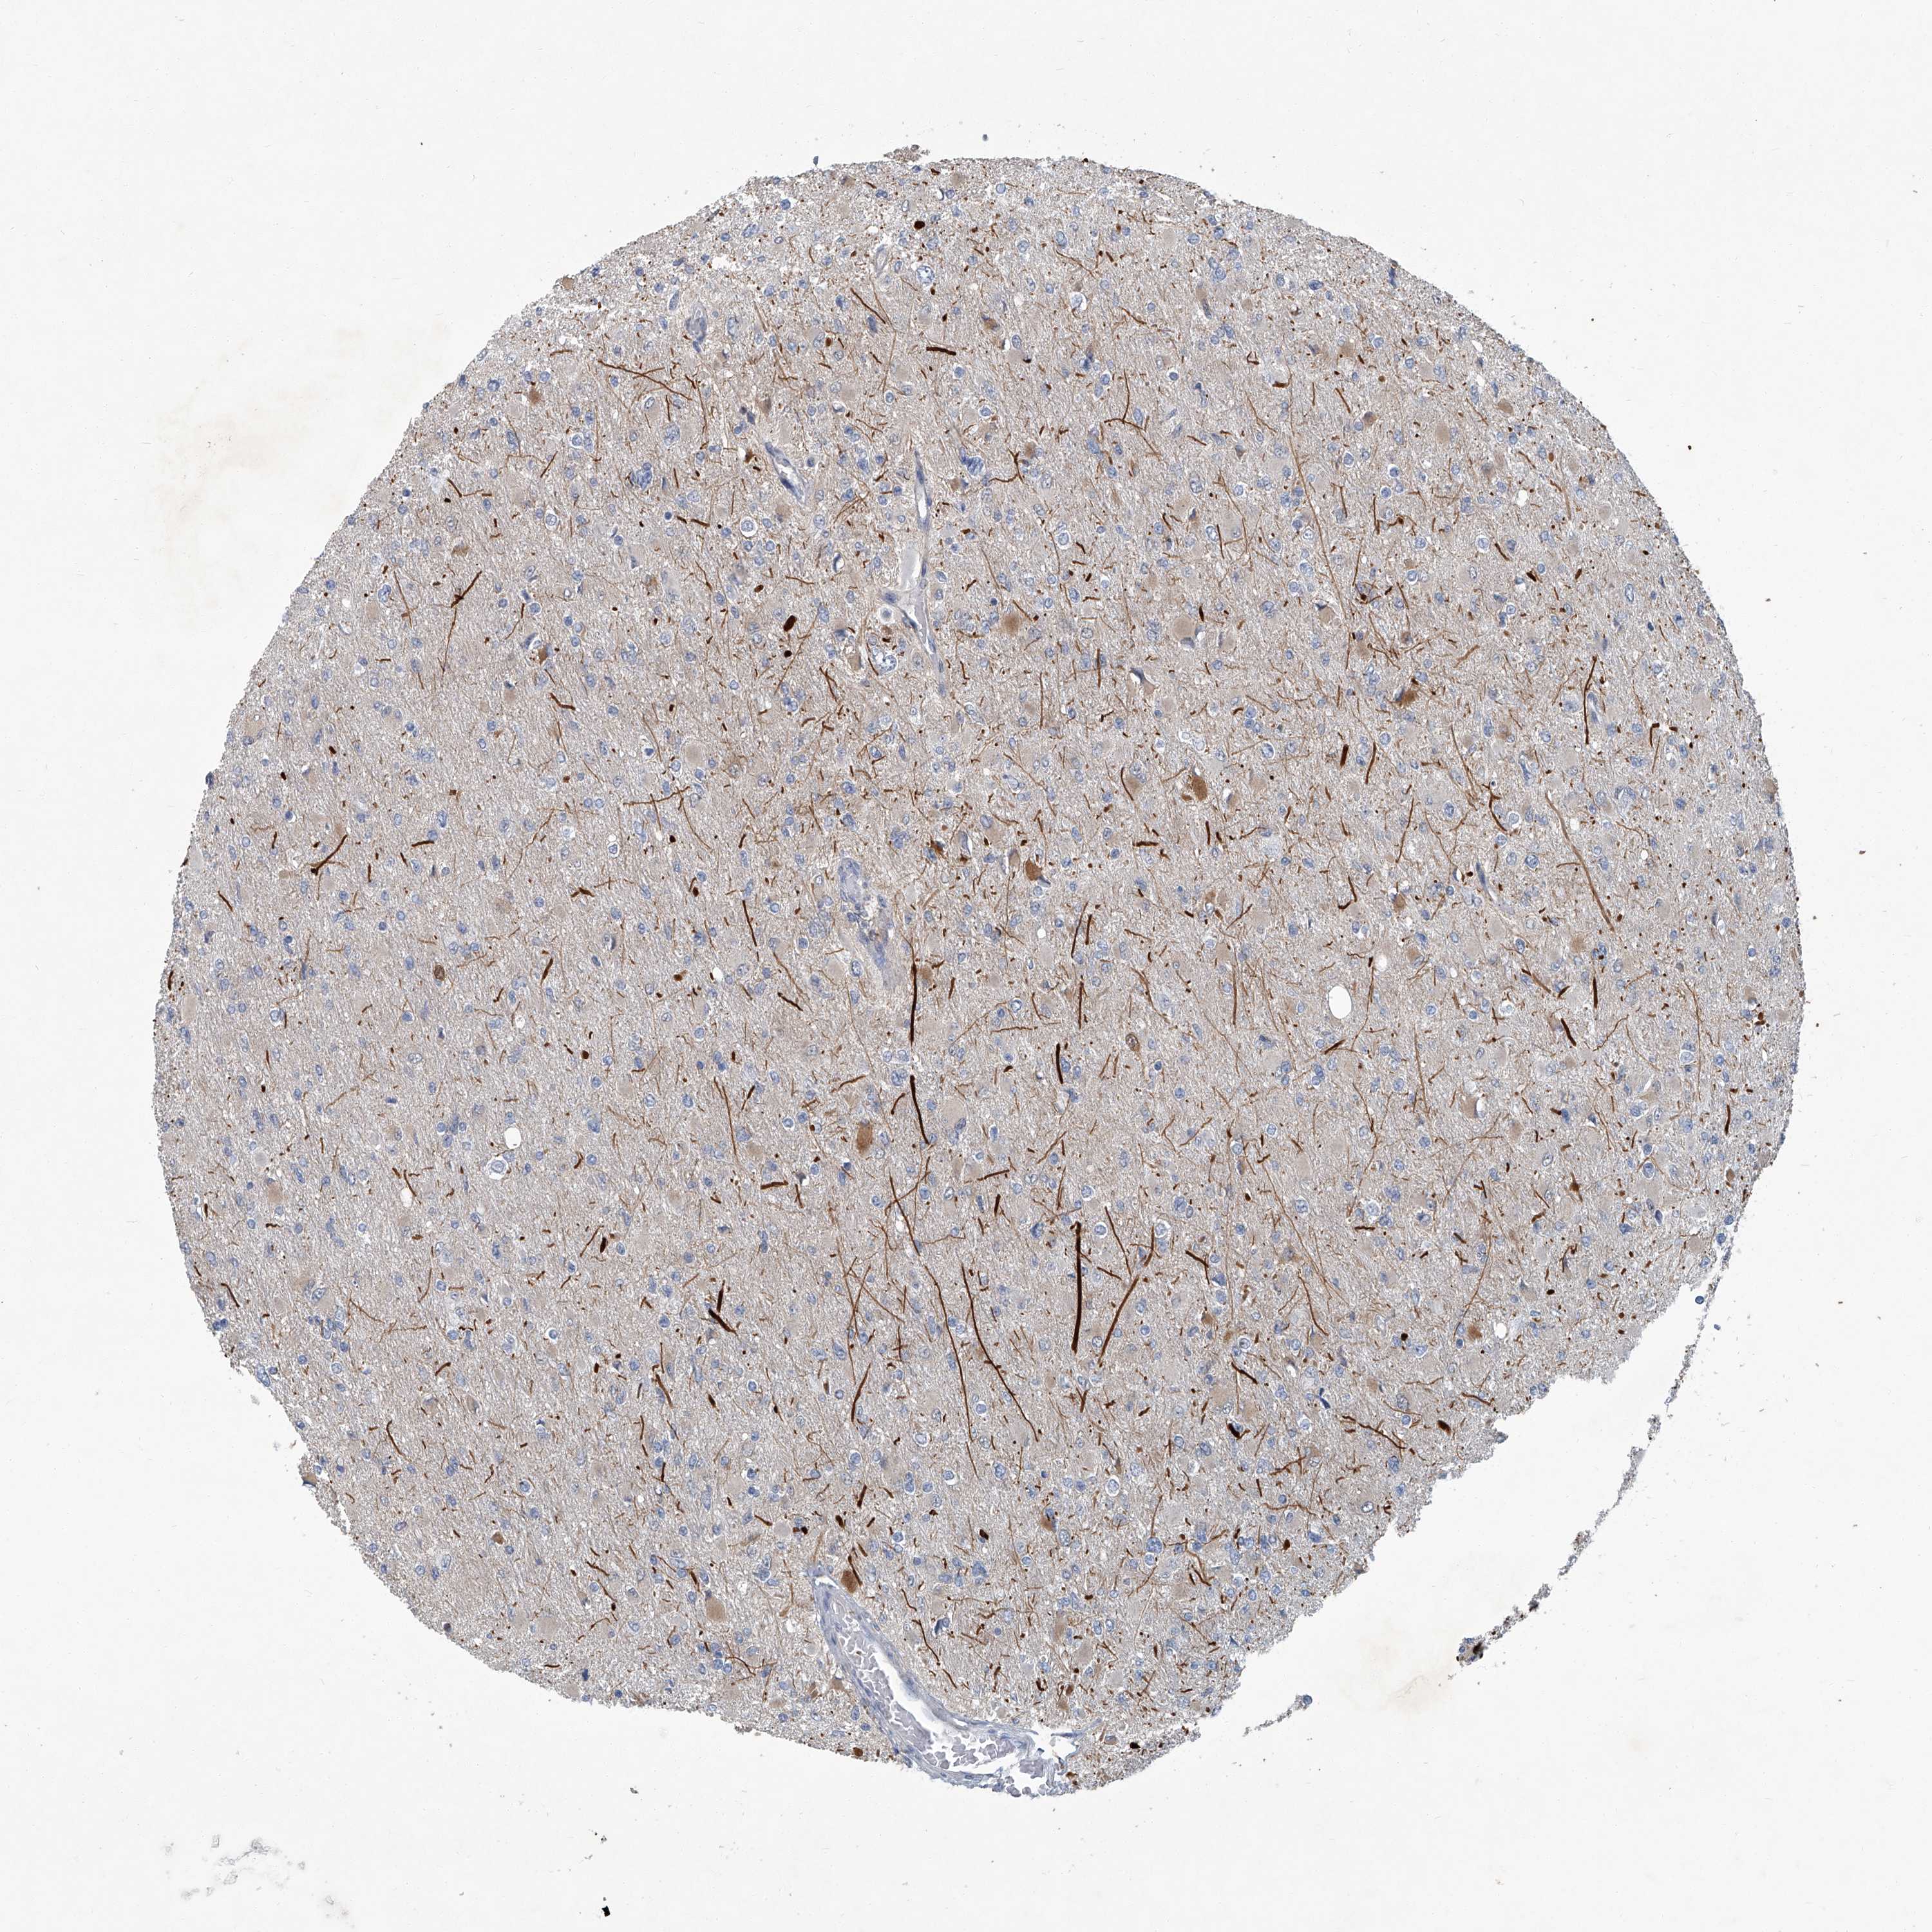

GLIOMA - Protein expressioni

A mouse-over function shows sample information and annotation data. Click on an image to view it in a full screen mode. Samples can be filtered based on level of antibody staining by selecting one or several of the following categories: high, medium, low and not detected. The assay and annotation is described here.

Note that samples used for immunohistochemistry by the Human Protein Atlas do not correspond to samples in the TCGA dataset.

Antibody stainingi

Antibody staining in the annotated cell types in the current human tissue is reported as not detected, low, medium, or high, based on conventional immunohistochemistry profiling in selected tissues. This score is based on the combination of the staining intensity and fraction of stained cells.

Each image is clickable and will lead to virtual microscopy that enables deeper exploration of all samples and also displays staining intensity scores, fraction scores and subcellular localization as well as patient and tissue information for each sample.

Antibody HPA030270

Antibody HPA030271

Antibody HPA030272

Staining

High

Medium

Low

Not detected

Intensity

Strong

Moderate

Weak

Negative

Quantity

>75%

75%-25%

<25%

None

Location

Nuclear

Cytoplasmic/membranous

Cytoplasmic/membranous,nuclear

Glioma, malignant, High grade

Glioma, malignant, Low grade

Glioblastoma, NOS